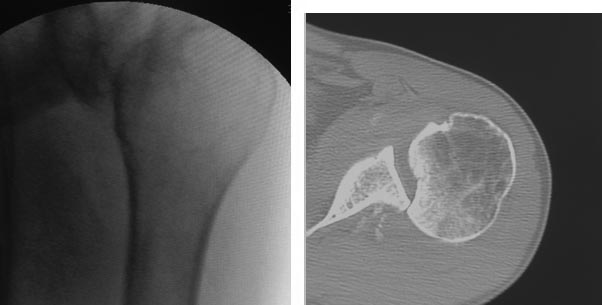

Мужчина около 40 лет. Задний вывих плеча. На момент госпитализации 2

месяца. Труд физический. Лечился амбулаторно с "ушибом". Варианты

оперативно лечения-

1 вправление вывиха и фиксация спицами.

2 Вправление вывиха и деротационная остеотомия плеча

3. Вправление вывиха и костная пластика

4. Вправление вывиха с транспозицией подлопаточной мышцы в зону костной

импрессии. Прошу голосовать